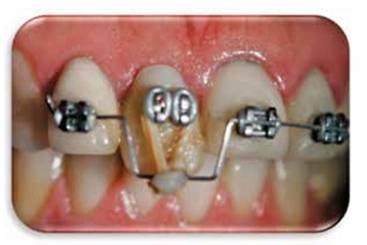

Se coloca una corona temporal de policarboxilato y se cementa.Se colocan brackets y un alambre de nitinol con un doblés a nivel de 1.1 para realizar tracción. (Figura 9)

Figura 9:  Se colocan brackets y un alambre rectangular de 17 x 25 de nitinol con un doblés a nivel de 1.1 para realizar tracción coronal.